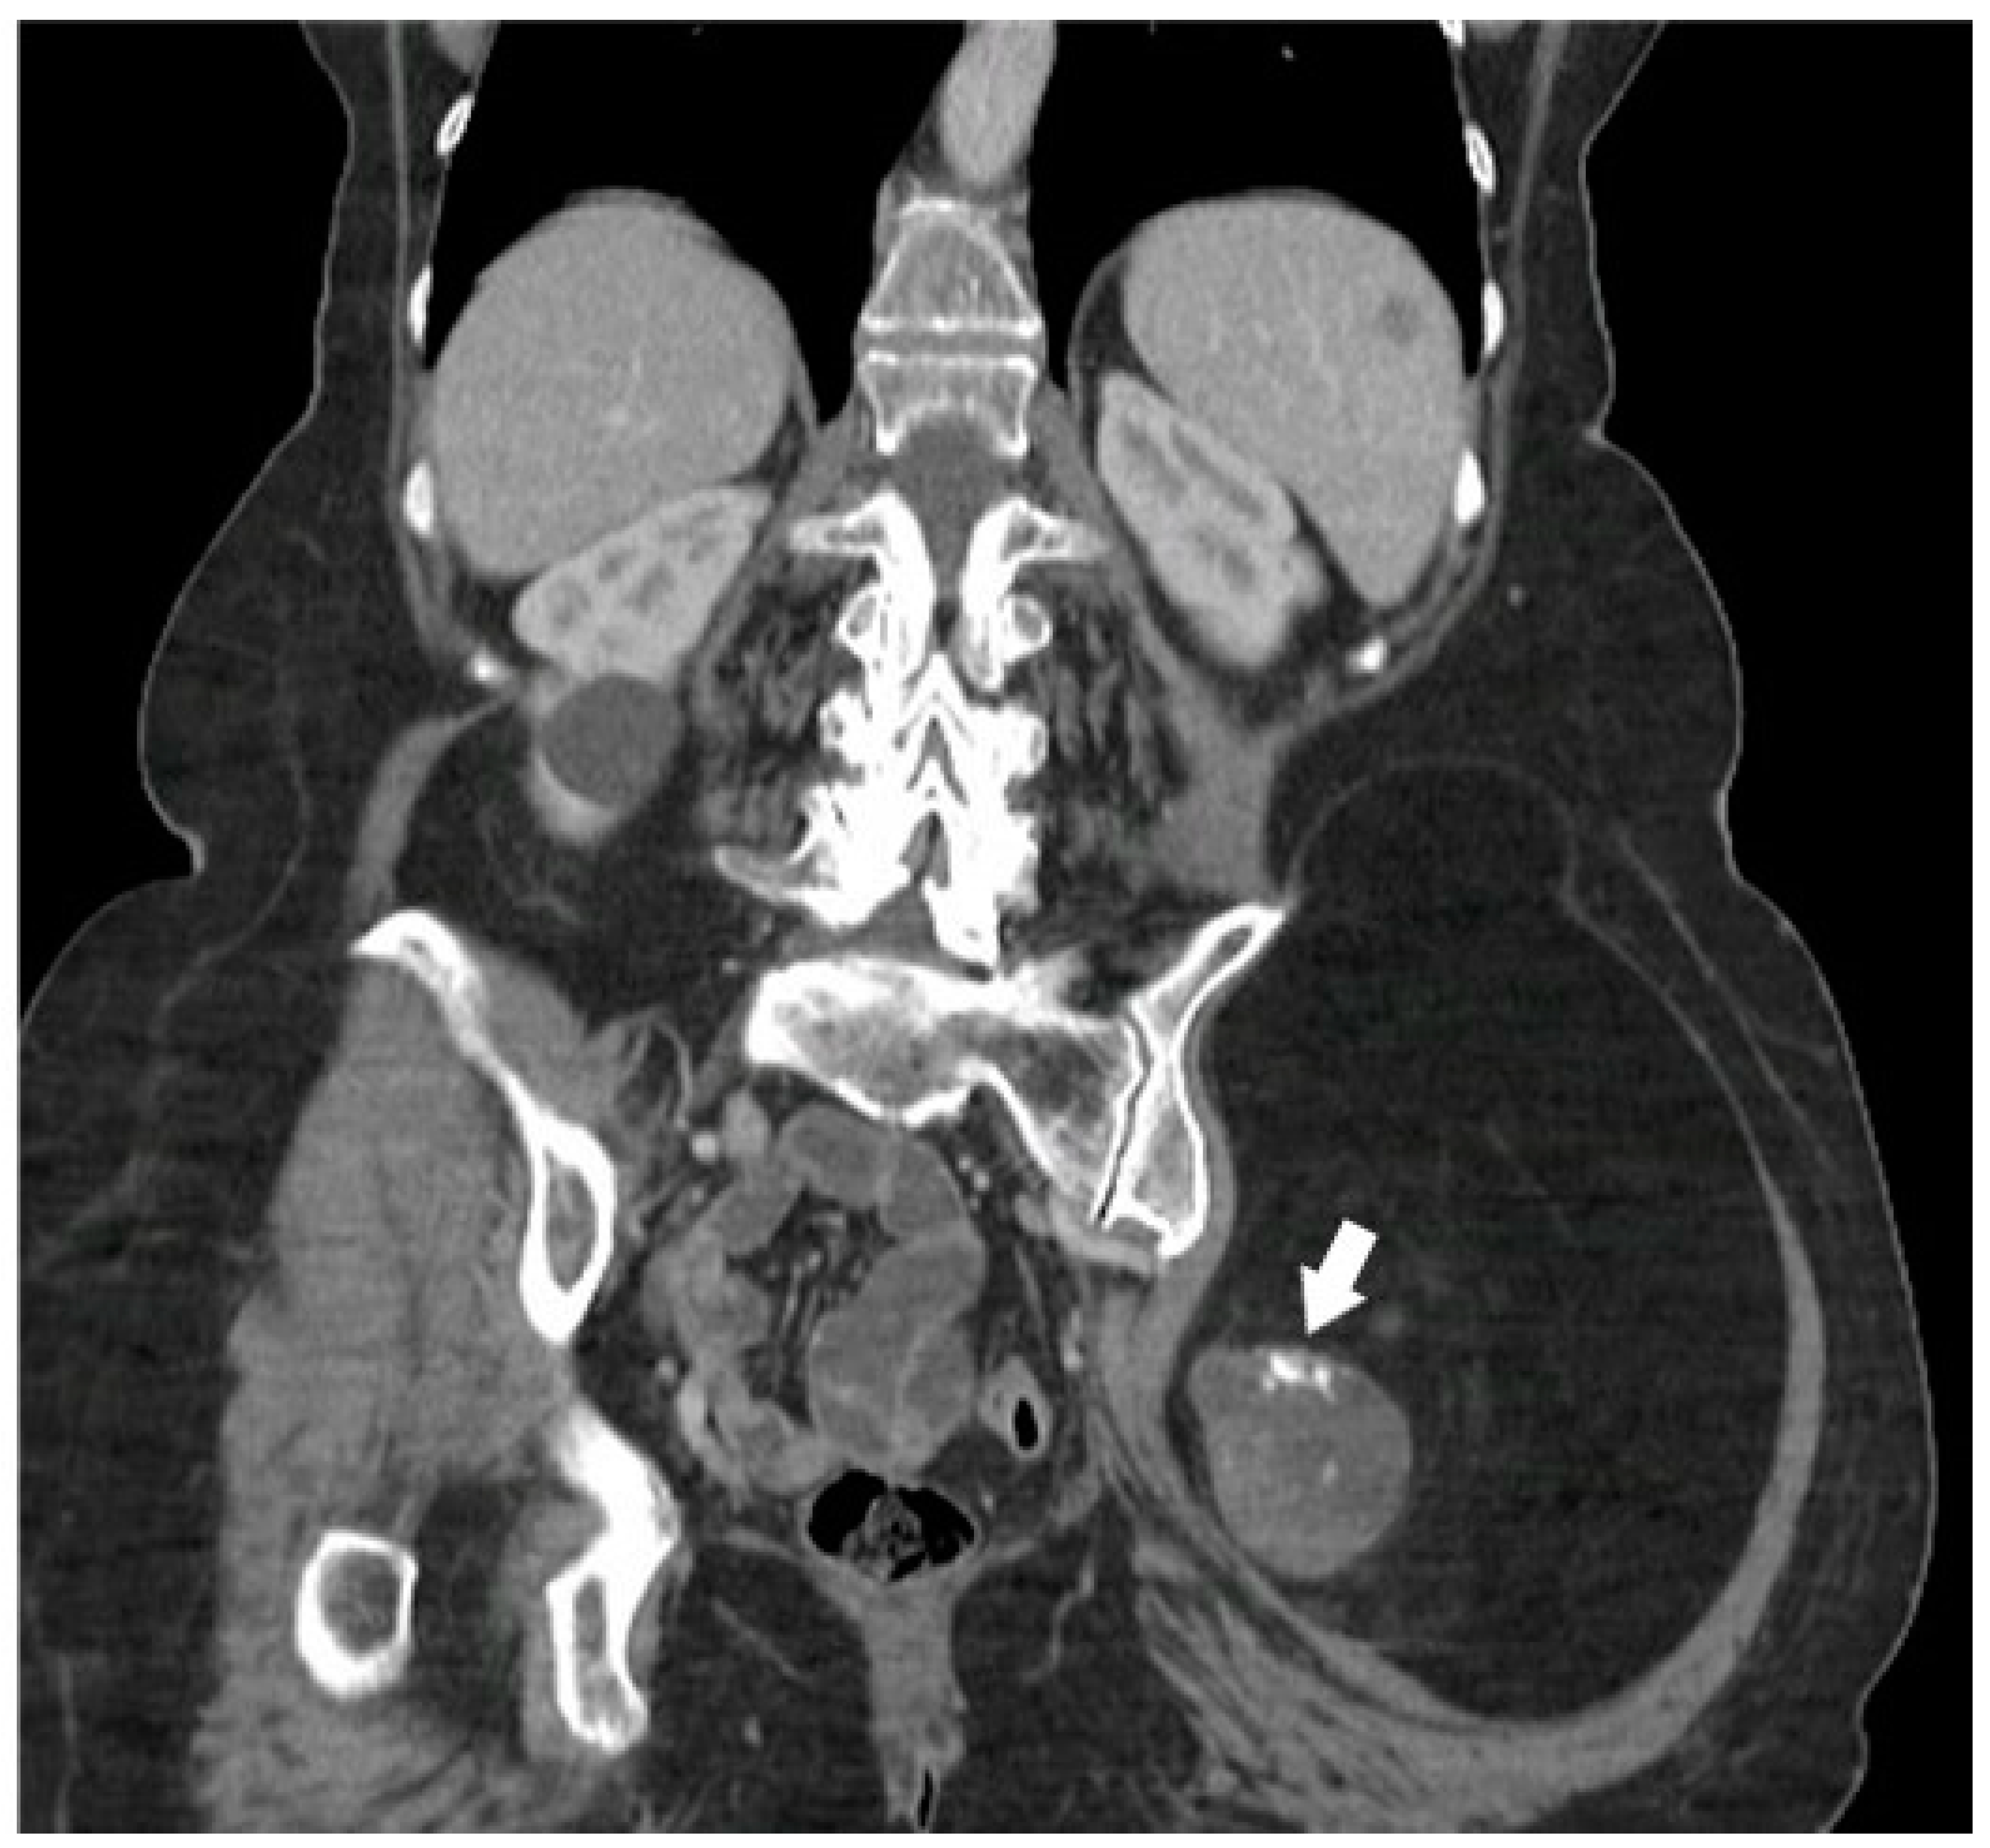

4.1. Adipocytic Tumors

- Henze, J.; Bauer, S. Liposarcomas. Hematol. Oncol. Clin. 2013, 27, 939–955. [Google Scholar] [CrossRef]

- O’Regan, K.N.; Jagannathan, J.; Krajewski, K.; Zukotynski, K.; Souza, F.; Wagner, A.J.; Ramaiya, N. Imaging of liposarcoma: Classification, patterns of tumor recurrence, and response to treatment. Am. J. Roentgenol. 2011, 197, W37–W43. [Google Scholar] [CrossRef]